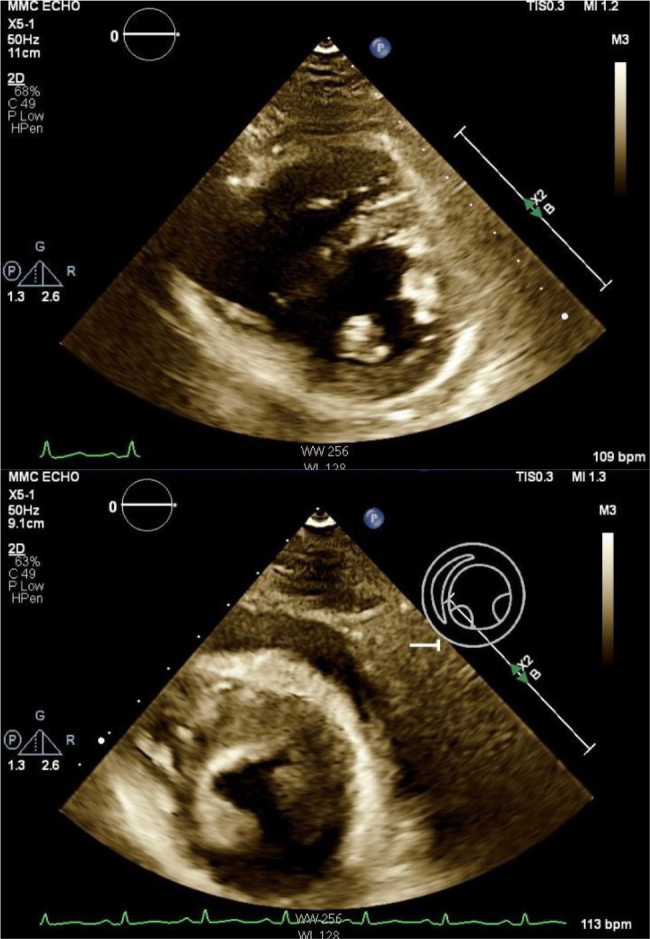

Case description: A 24-year-old female with cystic fibrosis, diagnosed at nine months, presented with two weeks of dyspnoea. Examination revealed bilateral rhonchi, facial oedema and non-pitting thigh oedema. Laboratory results showed a white blood cell count of 11.3 ×109/l, erythrocyte sedimentation rate of 99 mm/hr and C-reactive protein level of 45.3 mg/dl. Initially admitted for cystic fibrosis exacerbation, she was found to have pericardial effusion. Despite facial and lower extremity swelling, she denied cardiac symptoms. During hospitalisation, she developed haemodynamic instability requiring pericardiocentesis, with echocardiography confirming constrictive pericarditis. Chest computed tomography angiography showed pericardial calcifications; autoimmune workup was negative. She was discharged on colchicine with close follow-up.

Abstract Image